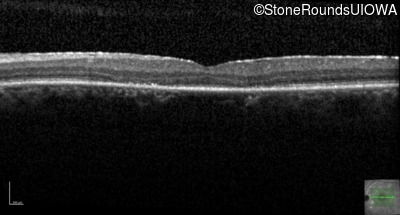

This 44 year old man became photophobic about 6 years ago. He has been taking Imuran since his kidney transplant 23 years ago.

| Age at visit: 47 years |

| Age at visit: 50 years |

| Senior-Loken Syndrome | NPHP1 | Gly343Arg G(GG)>A(GG) | Deletion of Entire Gene | AR |